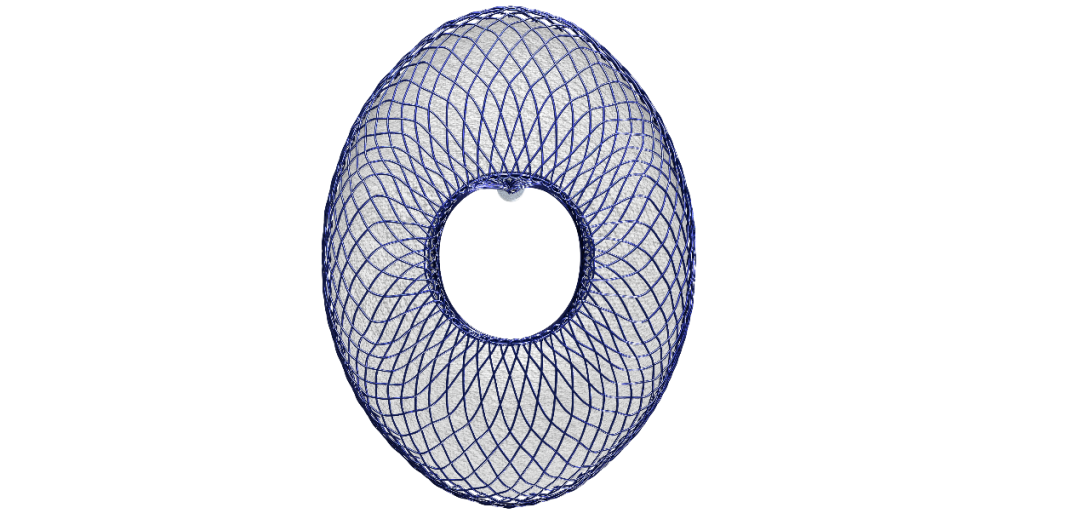

傲流医疗研发的FreeFlow®经皮房间隔分流系统是中国首款具有高分子膜快速内皮化,同时可二次回收的房间隔分流系统,独特的椭圆形设计减少了植入物的体积,同时可搭配较小的输送系统。该技术已申请多项专利,拥有完全的自主知识产权,是真正中国原研技术。